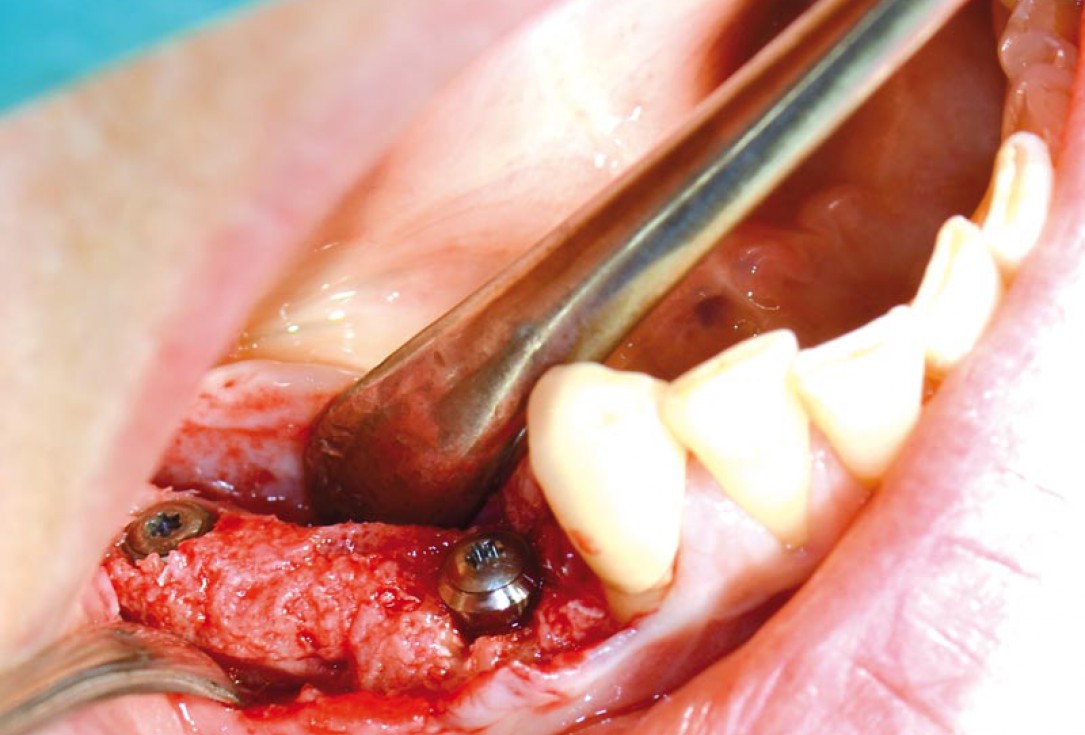

04/14 - Intraoperative situation: knife-edged ridge

Block augmentation with maxgraft® in the mandible - PD Dr. Dr. F. Kloss